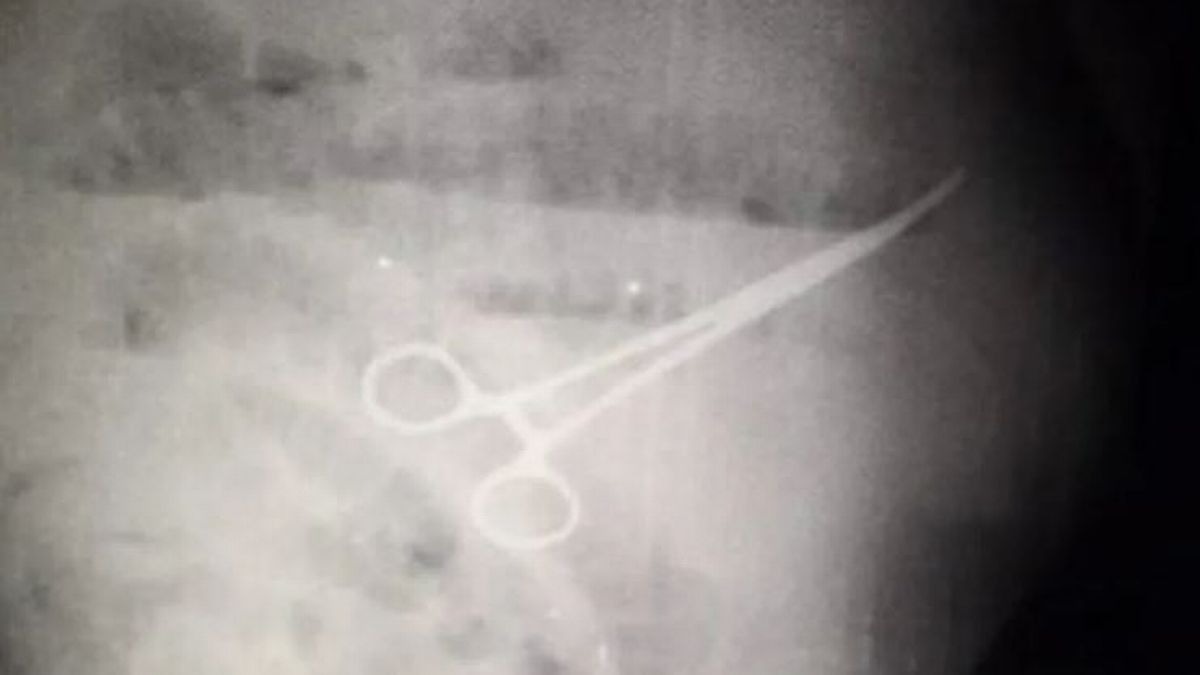

Bốn ngày sau các nhân viên y tế quyết định tiến hành chụp X-quang và phát hiện có một chiếc kéo đã bị bỏ quên trong dạ dày của bệnh nhân. Ông Chavez lại thêm một lần nữa phải tiến hành phẫu thuật khẩn cấp tuy nhiên ông đã tử vong sau đó 5 ngày, gia đình nạn nhân đã đổ lỗi cho các bác sĩ vì làm việc cẩu thả.